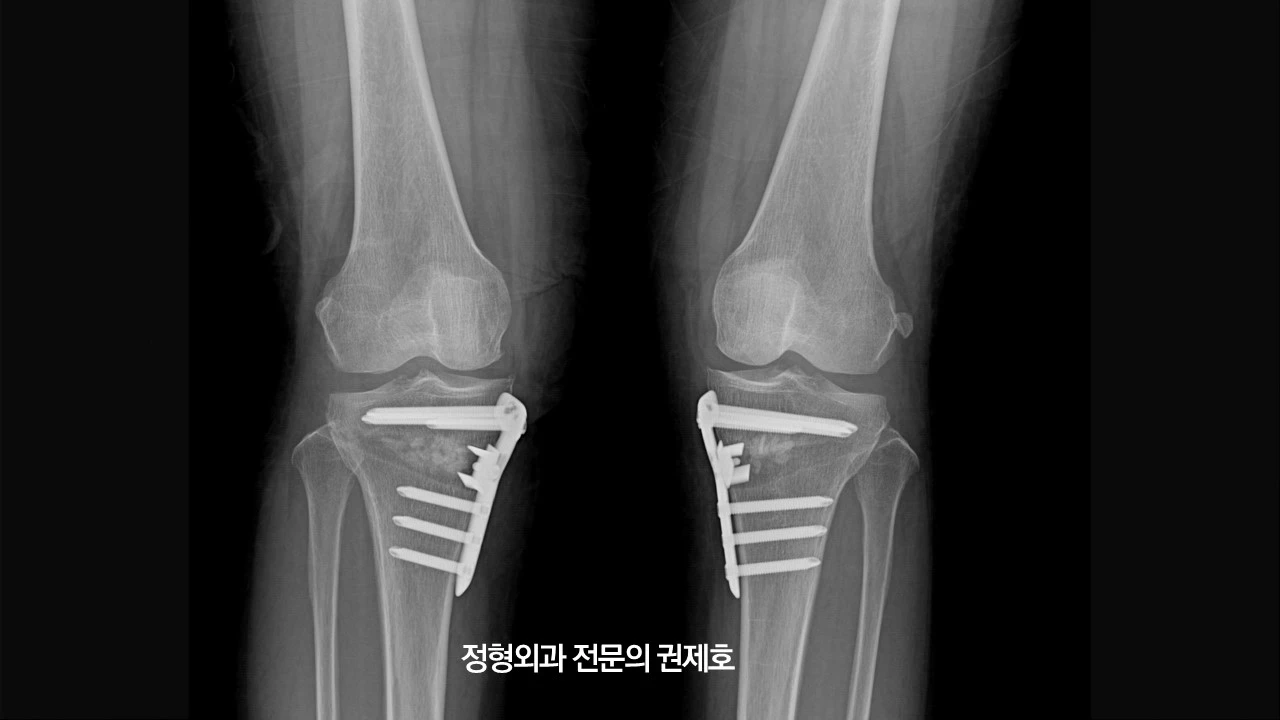

이렇게 무릎 절골술을 모두 마치게 되고 사진을 찍으면 금속판이 벌린 부분을 잡아주고 있는 모습으로 관찰되게 됩니다.

2주가 되면 서있을 수 있게 되기 때문에 하지 정렬 검사를 다시 시행하게 되고, 이때 교정이 잘 되었는지를 파악하게 됩니다.

무릎절골술의 변화

무릎 절골술이 무릎과 다리에 어떤 변화를 가져다주는지 확인해보도록 하겠습니다. (좌측) 처음 내원 당시 사진이고, 우측이 무릎절골술 2주 차의 사진입니다. 어떠신가요? 다리의 모양과 축의 변화가 느껴지시나요?

이게 바로 무릎절골술을 통해 다리의 열을 바꾸어 무릎관절염의 진행을 막으면서 동시에 무릎의 통증을 잡아주는 관절염 초기, 중기에 사용되는 수술 방법입니다.